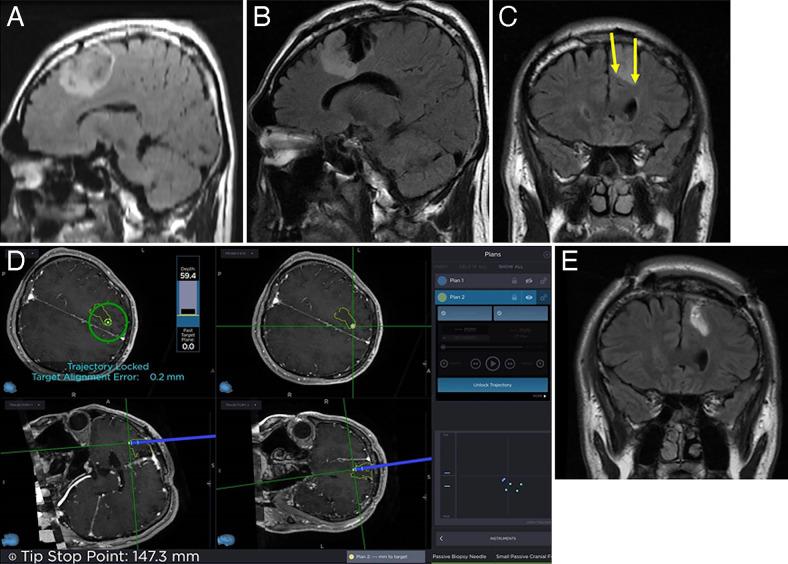

Surgery was performed using the StealthStation S8 linked to the Stealth Autoguide cranial robotic guidance platform and a high-resolution three-dimensional (3D) surgical microscope. A surgical plan was created to determine the removal area using fence-post tube placement at the tumor and normal brain tissue boundary. Using this surgical plan, the robotic system allowed quick and accurate fence-post tube positioning, automatic alignment of the needle insertion and measurement positions in the brain, and quick and accurate puncture needle insertion into the brain tumor. Use of a ventricular drainage tube for the outer needle cylinder allowed placement of the puncture needle in a single operation. Furthermore, use of a high-resolution 3D exoscope allowed the surgeon to simultaneously view the surgical field image and the navigation screen with minimal line-of-sight movement, which improved operative safety. The position memory function of the 3D exoscope allowed easy switching between the exoscope and the microscope and optimal field of view adjustment.

观察结果

手术使用与Stealth Autoguide颅骨机器人引导平台相连的StealthStation S8和高分辨率三维(3D)手术显微镜进行。制定手术计划,通过在肿瘤与正常脑组织边界处放置栅栏式导管来确定切除区域。利用该手术计划,机器人系统能够快速准确地进行栅栏式导管定位,自动对齐脑内针插入和测量位置,并将穿刺针快速准确地插入脑肿瘤。使用脑室引流管作为外针筒可在单次手术中放置穿刺针。此外,使用高分辨率3D外视镜可使外科医生以最小的视线移动同时查看手术视野图像和导航屏幕,从而提高了手术安全性。3D外视镜的位置记忆功能便于在外视镜和显微镜之间轻松切换并进行最佳视野调整。